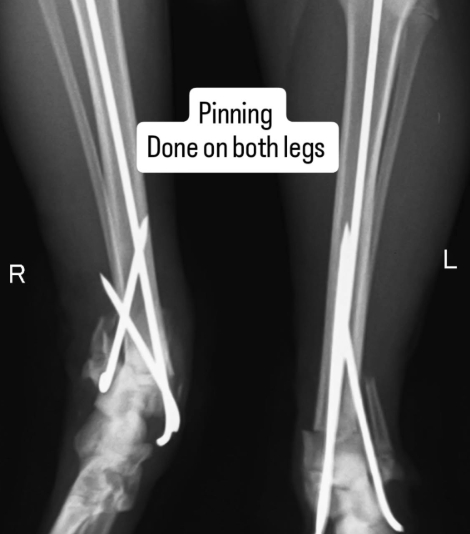

After going from pillar to post and getting no help, his feeder reached out to me. She had first aid done and was wondering what to do next as Timon needed urgent and intensive intervention. His bones were crushed and one was jutting out.

We got various opinions and decided to admit Timon at @petology_clinic where Timon underwent surgery yesterday.